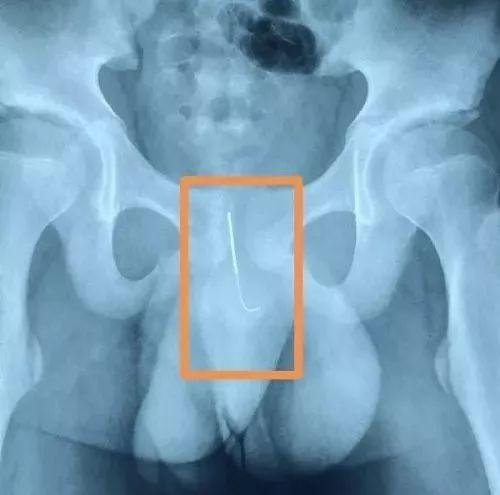

经过B超、X片检查,在其尿道部位发现了一根长达十几厘米的钢针,扎的位置很深,一头刺在了尿道壁上,差点进入膀胱。